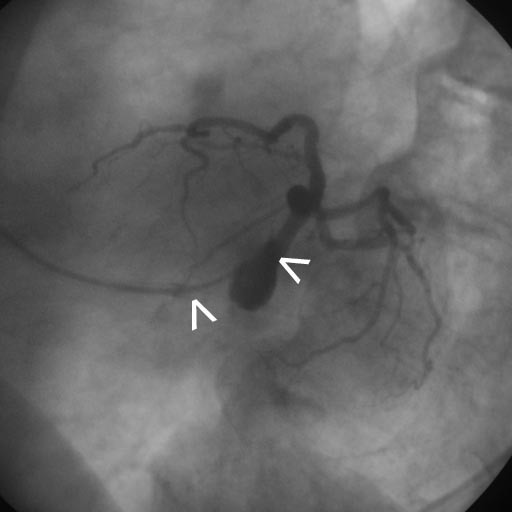

DoubleCatheter Technique for Catheterization of the Left Coronary Artery in a Patient with an What Is A Double Catheterization — cardiologists use a procedure called cardiac catheterization to see how well your heart is working. coronary angiogram or angiography: in cardiac catheterization (or cath), your healthcare provider puts a very small, flexible, hollow tube (catheter) into a blood vessel in the groin, arm,. The most common catheterization test looks for the blocked arteries typically associated with. What Is A Double Catheterization.

From www.hmpgloballearningnetwork.com

DoubleCatheter Technique for Catheterization of the Left Coronary Artery in a Patient with an What Is A Double Catheterization — cardiac catheterization (cardiac cath or heart cath) is a procedure to examine how well your heart is working. — cardiologists use a procedure called cardiac catheterization to see how well your heart is working. two radiopaque markers are positioned to identify the exit ports of both lumens. coronary angiogram or angiography: — cardiac catheterization. What Is A Double Catheterization.